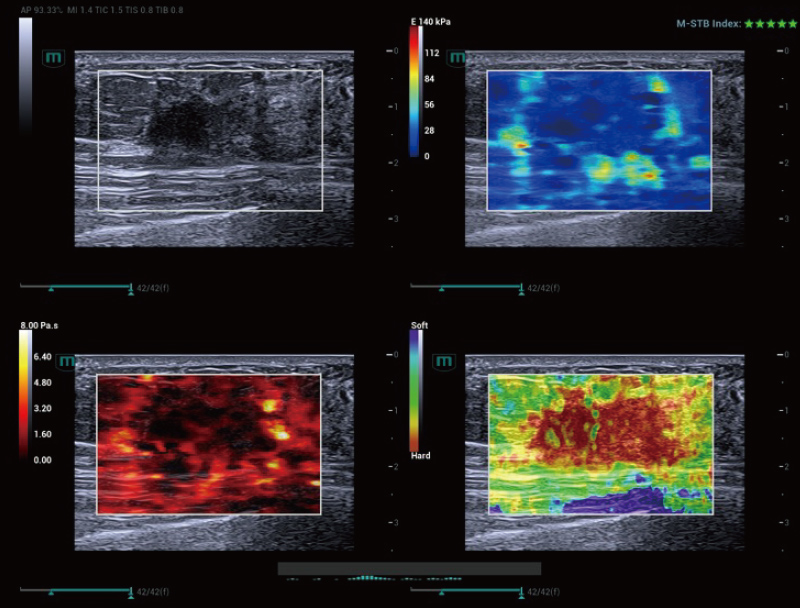

La STE riscrive i confini delle prestazioni dell'imaging. Grazie a molteplici strumenti intelligenti e di controllo della qualità, il sistema valuta in modo intuitivo e quantitativo la rigidità dei tessuti, rendendolo altamente efficace per la valutazione della fibrosi epatica e del tumore al seno.

Prestazioni di imaging superiori

Strumenti di controllo qualità multipli

Strumenti intelligenti

Carcinoma mammario, STE

Carcinoma mammario | STE

M-Reference

M-Reference è uno strumento di analisi combinata multiparametrica che consente la diagnosi multiparametrica in tempo reale, nello stesso settore e nella stessa vista. A differenza dell'ecografia singola tradizionale, offre informazioni diagnostiche multidimensionali e indicatori di valutazione quantitativa delle malattie.

Analisi combinata multiparametrica

Strumenti di quantificazione multiparametrica

Valutazioni in tempo reale, in un'unica schermata

Massa mammaria, M-Reference

Massa mammaria